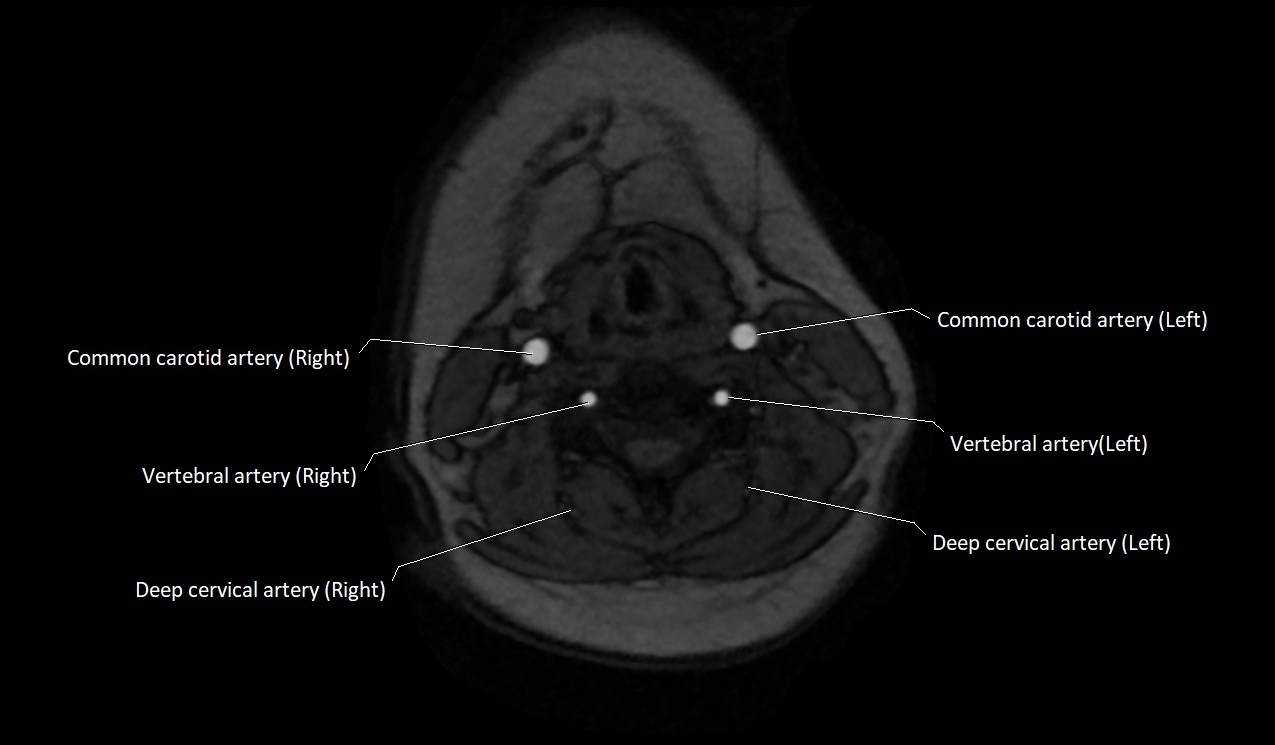

MRI images

image